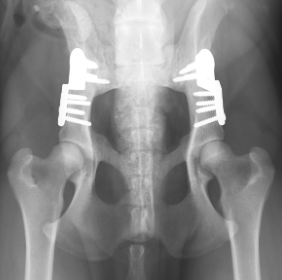

- Τριπλή η διπλή οστεοτομή της πυέλου (TPO /DPO): Ενδείκνυται σε σκύλους ηλικίας 7 έως και 11 μηνών (TPO) με απουσία δευτερογενούς οστεοαρθρίτιδας (Εικόνα 2).

Οι παραπάνω τεχνικές αλλάζουν την ανατομία της πυέλου, ώστε η κοτύλη να “σκεπάσει” καλύτερα την κεφαλή του μηριαίου. Διορθώνοντας την αρθρική χαλαρότητα παρεμποδίζεται ο φαύλος κύκλος της ανώμαλης τριβής των αρθρικών χόνδρων καθώς και οι καταστροφικές συνέπειες αυτού για την άρθρωση.